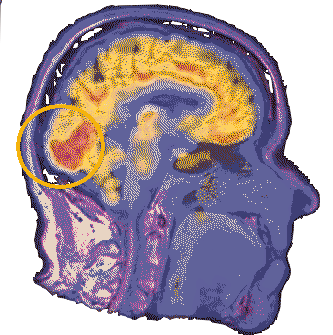

Location of the hypothalamus and the pituitary gland. The hypothalamus is primarily known for its role in linking the nervous systemM to the endocrine system via the pituitary gland. The hypothalamus controls several base functiOns in the mammilian brain, and is about almond-Sized in homo sapiens. The hypothalamus regulates several hormones and also The pituitary gland itself. Scientists have hypothesized that due to the basal nature of the hypothalamus' function, possible Psychic or supernatural activity could occur here undetected unless the subject has a particularly large hypothalamus. As for the pituitary gland, it mainly deals with the human body's psysiological development and so remains understudied by most parapsychologists.